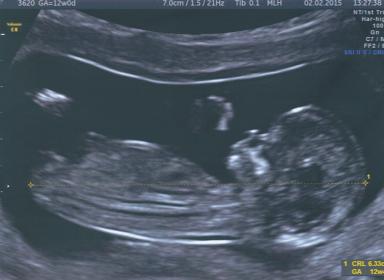

Not sure if I've attached this correctly but would love to know anyone's guess as to possible girl or boy ?? Tech said girl - which would be amazing and would complete our family (already have my little prince) - but my gut is saying boy.....

Sarah x